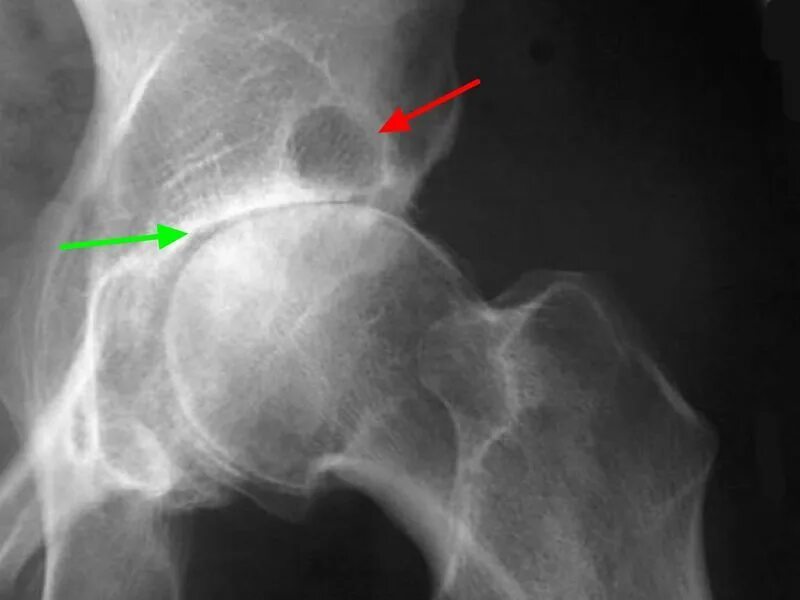

Доа тазобедренного сустава 2 степени